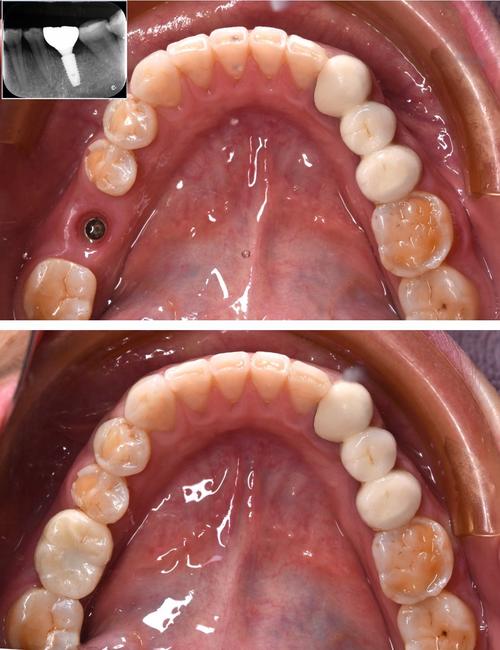

种牙流程严格遵循医疗规范,通常分为五个阶段:第一阶段为术前检查,包括口腔检查、CBCT影像学检查、血常规及凝血功能检测,评估全身健康状况及骨条件;第二阶段为方案设计,医生与患者充分沟通,根据缺牙位置、骨量、经济预算制定个性化方案;第三阶段为手术植入,在局部麻醉下,通过导板引导将种植体植入牙槽骨,手术时间单颗约30-60分钟,创伤小、出血少;第四阶段为骨愈合期,一般需3-6个月,期间种植体与牙槽骨形成骨结合;第五阶段为修复戴牙,愈合后取模制作牙冠,试戴调整后完成最终修复,恢复咀嚼功能与美观。